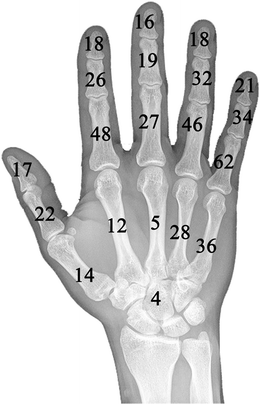

Enchondroma Hand

Enchondroma - Azouz Hand SurgeryAzouz Hand Surgery Enchondromas - Pathology - Orthobullets LearningRadiology- Enchondroma Enchondroma-of-hand LearningRadiology- Enchondroma Enchondroma Hand